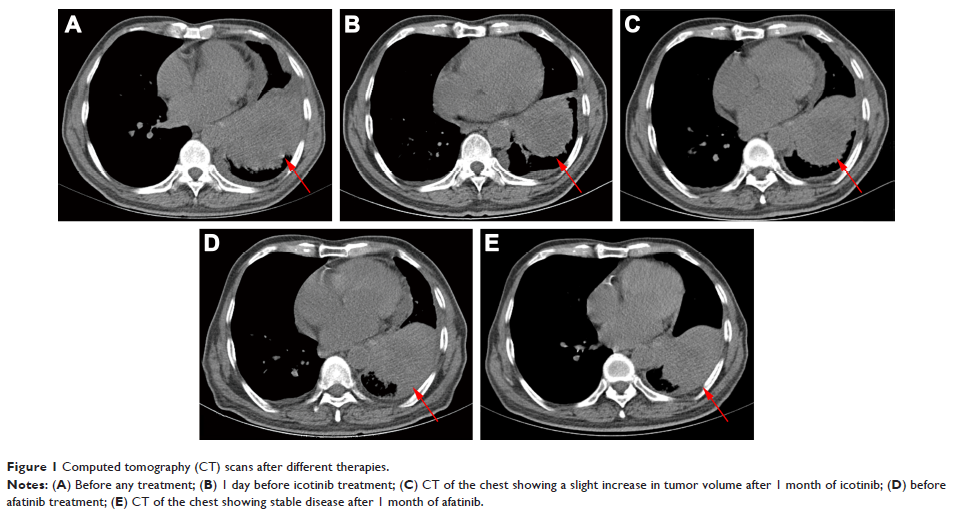

Case Report

- 作者:Yan Gao, Aihong Zheng, Xiuming Zhu, Jia Song, Qian Xue

- 期刊:OncoTargets and Therapy